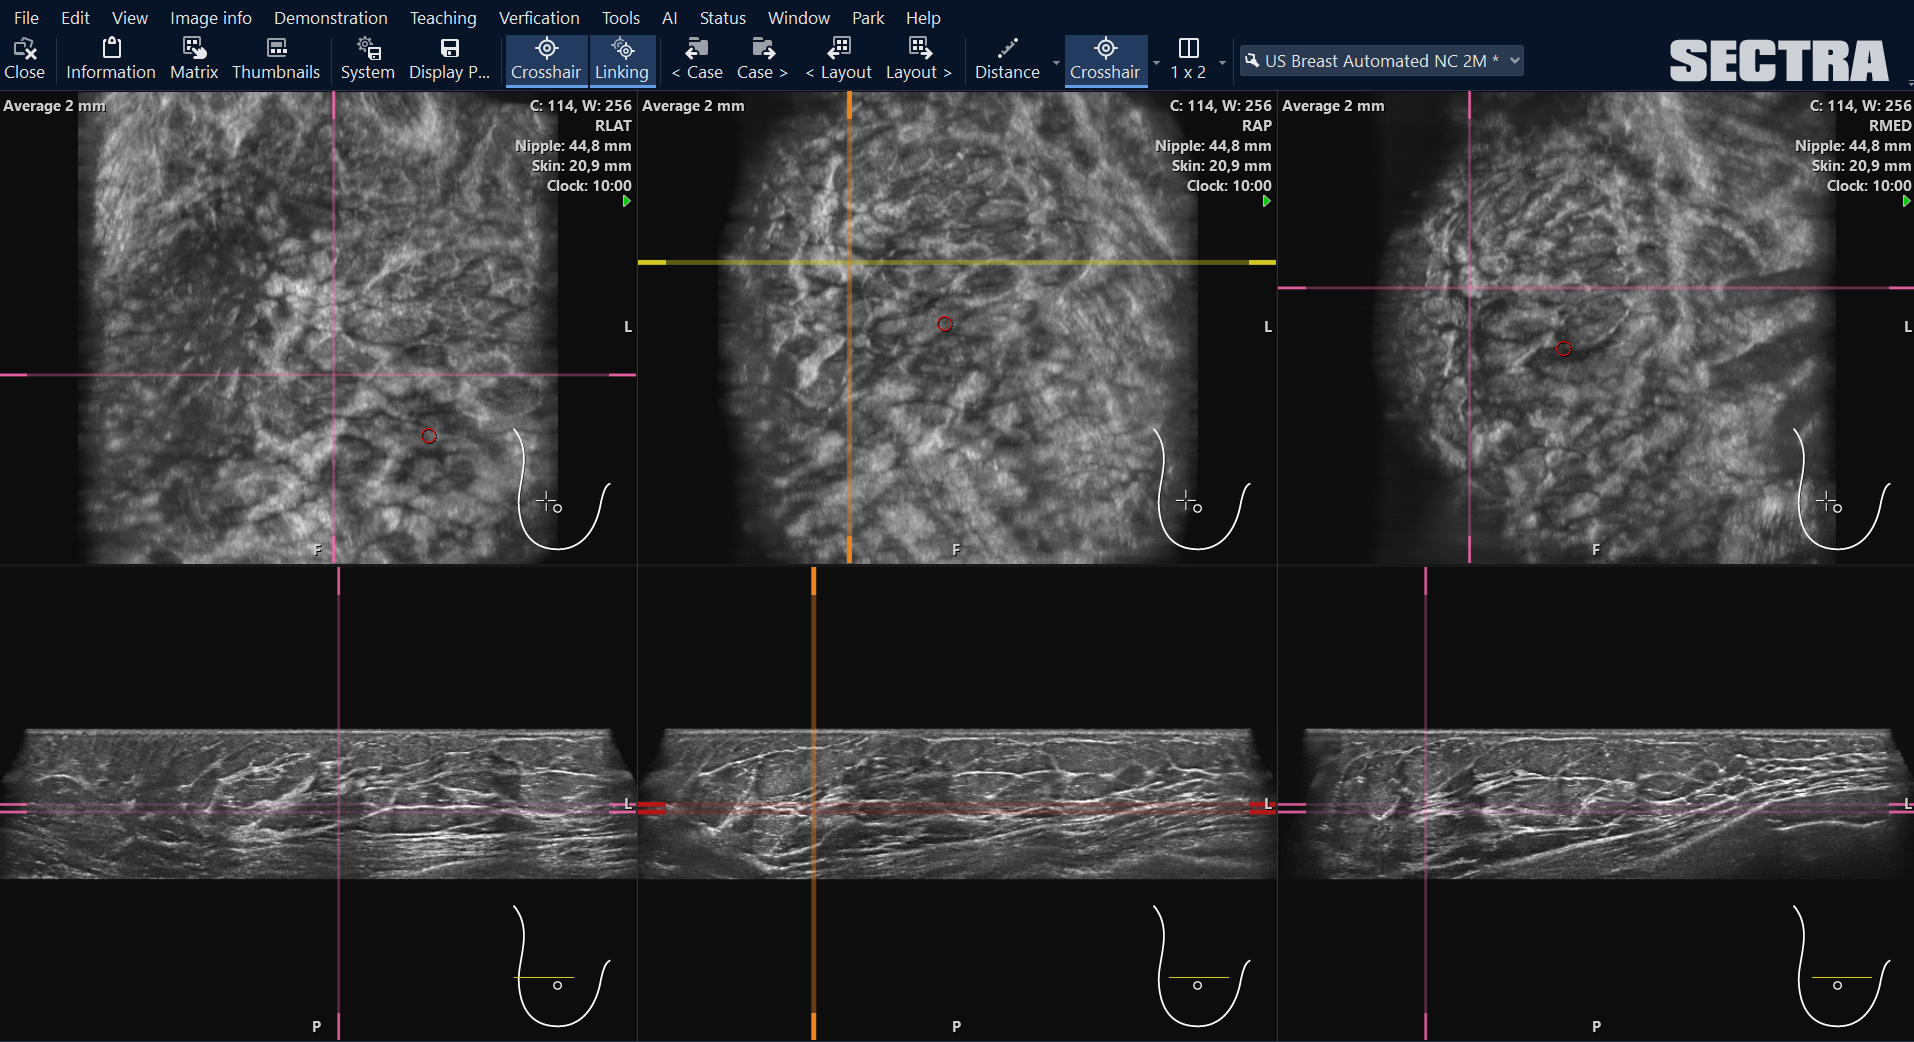

Zur Auswertung von automatisierten Brustultraschallbildern (ABUS), bietet Sectra die Möglichkeit einer multiplanaren Rekonstruktion (MPR). Die Funktion ist vollintegriert in die Mammographie-Befundoberfläche (IDS7/mx). Bisher konnte auf die Bilder ausschließlich mit speziellen Anwendungen oder über dedizierte Workstations zugegriffen werden, die als Zusatz zu der ABUS-Untersuchungseinheit erworben wurden. Durch diese neue Funktion sorgt Sectra dafür, dass die Bilddaten an jedem beliebigen Mammographie-Befundarztarbeitsplatz und unabhängig vom Standort ausgewertet werden können. Mit der Entwicklung und Integration der MPR–Funktion für ABUS-Aufnahmen macht Sectra die dedizierten Workstations des Bildherstellers obsolet. Damit setzt das schwedische Medizintechnik-Unternehmen seine Vision, alle Bilddaten in einem System zusammenzufassen, weiter in die Tat um.

Gestaltet wurde die neue Funktionalität in Zusammenarbeit mit Fachärzten der Partnerschaftsgesellschaft DIE RADIOLOGIE, einem der größten Zentren für die Untersuchung und Diagnose von Brusterkrankungen im Raum München und einer der wenigen Standorte in Deutschland, an denen eine Untersuchung mit einem ABUS-Scanner angeboten wird. Das Gerät tastet die Brust automatisiert ab und generiert hunderte von Schichtaufnahmen, die eine multiplanare Darstellung in den verschiedenen Raumebenen erlaubt.

Für die Visualisierung der Volumendatensätze bedarf es eines Arbeitsplatzes, der über die notwendigen technischen Komponenten und Funktionalitäten verfügt. Anwender können entweder die dazugehörige Workstation des gleichen Herstellers – so wie die Münchner es bisher mit dem ABUS-System gehandhabt haben – oder sie direkt vollintegriert in der Sectra Lösung nutzen. Unterstützt wird dies zusätzlich durch dynamische Anzeigeprotokolle.

Sectra ist es nun gelungen, die Funktionalität für automatisierten Brustultraschall in ihr PACS zu integrieren. So kann der Datensatz direkt im digitalen Bildarchiv visualisiert und analysiert werden – ohne Zwischenschritte. Für das Team eine enorme Zeitersparnis, freut sich Thomas Hilbertz: “Wir sind eine große Einheit. Teilweise führen sieben, acht Kolleg*innen zeitgleich die Brustdiagnostik durch. Es erleichtert die Arbeit deutlich, wenn von jedem Standort aus auf die Schichtbilder zugegriffen werden kann. Zum Beispiel auch, wenn man einen auffälligen Befund im ABUS diagnostiziert hatte und zwei Wochen später eine Biopsie durchführen möchte. Das Langzeitarchiv von Sectra hält hierzu alle Voruntersuchungen bereit. Besondere Unterstützung für den Vergleich bietet das punktgenaue Verlinken von aktueller und Voruntersuchung auch mit MPR-Rekonstruktionen.“